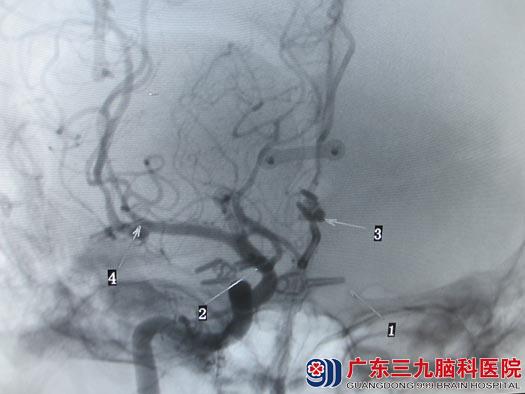

考虑介入治疗不能一次性栓塞完全,且费用较大,家属选择手术治疗。由于破裂动脉瘤为右侧后交通动脉瘤,鲁明主任主刀在全麻下行右侧翼点入路双侧后交通、右侧大脑中动脉、右侧大脑前动脉多发动脉瘤开颅夹闭术,术中显微镜下成功一次性夹闭四个动脉瘤,术中出血少,经过顺利。术后朱女士恢复很快,复查DSA提示动脉瘤夹闭完全,载瘤动脉完好,康复出院。

术后造影